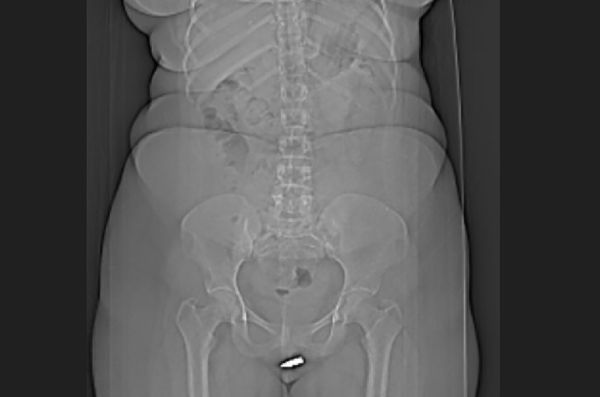

(图:互联网)

事发时24岁的女子坐在客厅中,下体突感到一阵剧痛,原来一颗子弹突然穿透天花板射中她,她被家人紧急送到摩加迪休市一家医院,断层扫描显示一颗子弹卡在阴蒂中,需要动手术才能取出。外科医生将患者局部麻醉后,顺利从私处取出子弹,女子休养后隔天便出院,一个月后回诊也没有并发症。

撰写报告的学者写道,“据我们所知,子弹卡阴蒂内的案例是史上首例”。

报告指出,非妊娠原因造成的“外阴外伤”十分罕见,通常造成原因可能与运动、烧伤、动物攻击或性侵有关,幸好子弹是低速射入女子体内,才没有造成更严重的伤害。